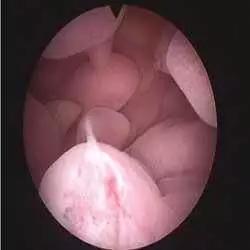

宫腔镜下见到的内膜息肉